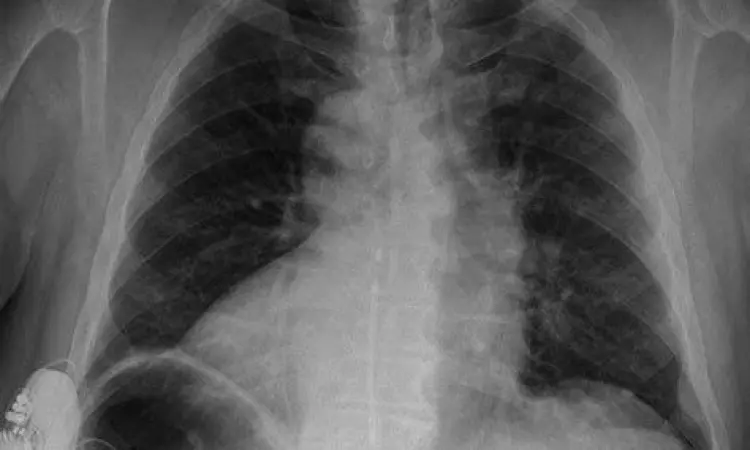

Secara anatomi, letak jantung manusia berada di dalam rongga dada, tepatnya di antara kedua paru-paru. Area ini dikenal dalam dunia medis sebagai mediastinum. Meskipun jantung memang condong ke arah kiri, dasar atau basis jantung sebenarnya berada di posisi yang cukup sentral. Memahami koordinat tepat dari organ ini tidak hanya penting bagi tenaga medis, tetapi juga bagi kita semua agar bisa lebih peka terhadap sinyal-sinyal kesehatan yang dikirimkan oleh tubuh, terutama saat merasakan ketidaknyamanan di area dada.

Jika kita meninjau lebih dalam, letak jantung manusia berada di belakang tulang dada (sternum) dan sedikit ke kiri dari garis tengah tubuh. Secara teknis, jantung terletak di atas diafragma, yaitu otot lebar yang memisahkan rongga dada dengan rongga perut. Posisi jantung ini sangat terlindungi oleh sangkar tulang rusuk (thoracic cage), yang berfungsi sebagai perisai alami terhadap benturan fisik dari luar.

Ujung bawah jantung yang berbentuk agak runcing disebut sebagai apex. Bagian apex ini mengarah ke bawah, ke depan, dan ke sisi kiri tubuh. Inilah alasan utama mengapa denyut jantung paling kuat seringkali dirasakan di sisi kiri dada, sehingga banyak orang menyimpulkan secara sederhana bahwa jantung berada di sebelah kiri. Padahal, sekitar sepertiga massa jantung berada di sisi kanan garis tengah tubuh, sementara dua pertiganya berada di sisi kiri.

Meskipun mayoritas orang memiliki letak jantung manusia yang normal (levocardia), terdapat variasi langka yang dikenal sebagai dextrocardia. Dalam kondisi ini, jantung seseorang justru terletak di sisi kanan rongga dada. Kondisi ini bisa terjadi secara mandiri atau sebagai bagian dari situs inversus, di mana seluruh organ dalam tubuh berada pada posisi cermin dari posisi normalnya.

Dextrocardia biasanya bersifat kongenital atau bawaan sejak lahir. Sebagian besar orang dengan kondisi ini dapat hidup normal tanpa gejala, namun pada beberapa kasus, hal ini bisa disertai dengan kelainan struktur jantung lainnya yang memerlukan pemantauan medis rutin. Mengetahui anomali ini sangat penting terutama saat melakukan pemeriksaan EKG atau tindakan bedah agar tidak terjadi kesalahan diagnosis.